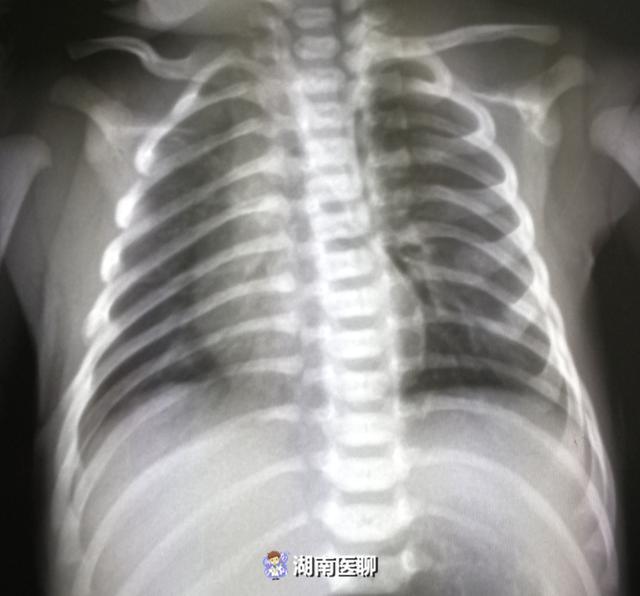

小儿胸片10,未见明显异常,建议随诊复查?